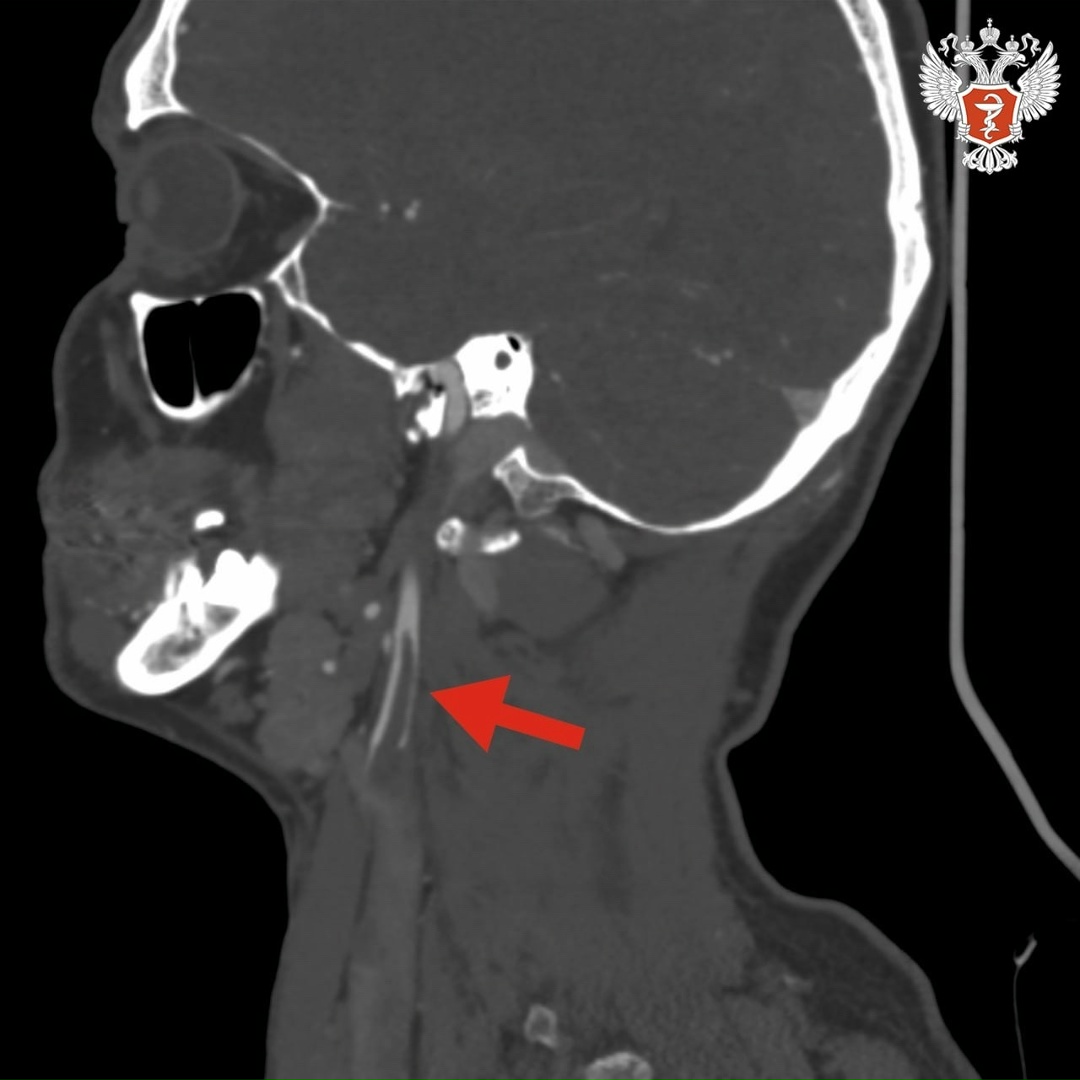

➡️ В ходе исследований врачи выявили тромб длиной около 4 см в просвете правой внутренней сонной артерии. Он нарушал кровоснабжение головного мозга. В любой момент тромб мог оторваться и закрыть магистральные артерии правого полушария, что привело бы к обширному ишемическому инсульту.

Хирурги экстренно провели операцию и удалили тромб, изъязвленную атеросклеротическую бляшку во внутренней и общей сонных артериях и восстановили анатомию сосудов.